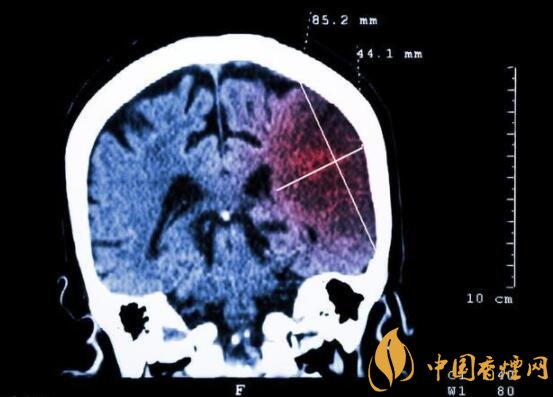

一般而言,急性脑梗塞与长期吸烟有非常密切的联系。有长期烟龄遇到肢体活动不顺,做头颅核磁共振检查往往查出一侧大脑中动脉闭塞的可能性很高。由此可见,吸烟确实与中风存在一定联系。